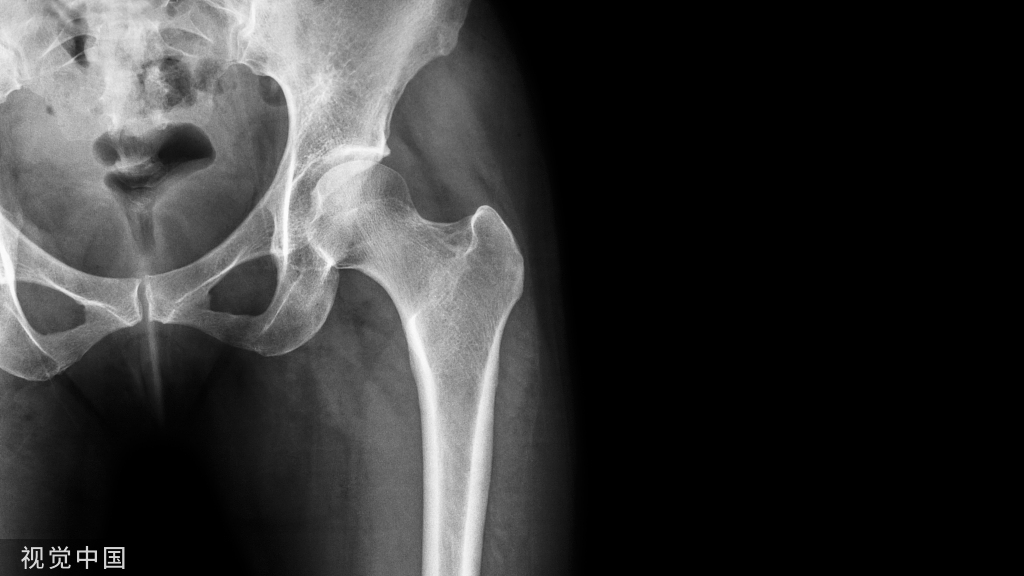

椎体夹心饼征:在X线平片上,胸腰椎椎体上、下缘终板各形成一条硬化带,每个椎体中心可见一条透明带,相互并行的硬化带和透明带与英式橄榄球衫(rugby sweater)上的条纹类似,西方学者称之为橄榄球衫椎体(rugger jersey spine)。这种两条硬化带中夹一条透明带的表现与中国的夹心饼亦相似,国内学者称之为夹心饼征。椎体终板上下缘的硬化带代表过多的骨样物质沉积,虽然它们的骨化并不充分,但这些骨样组织与正常椎体相比密度增加,在Ⅹ线照片上显示为不透光性,常为慢性肾衰竭所致